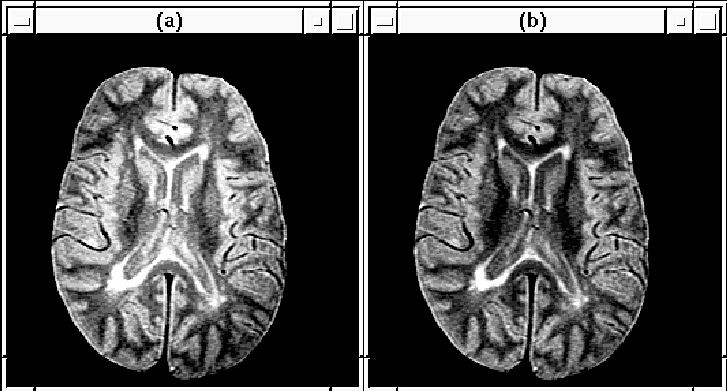

Figure 8.26 shows the RF inhomogeneity detected in Data Set 1 by the Correct Intensity process. Slice 16 of the PD-weighted volume, before and after intensity correction, is highlighted in Figure 8.27.

Figure 8.27: Slice 16 of MRI Data Set 1 (a) before

and (b) after RF correction.